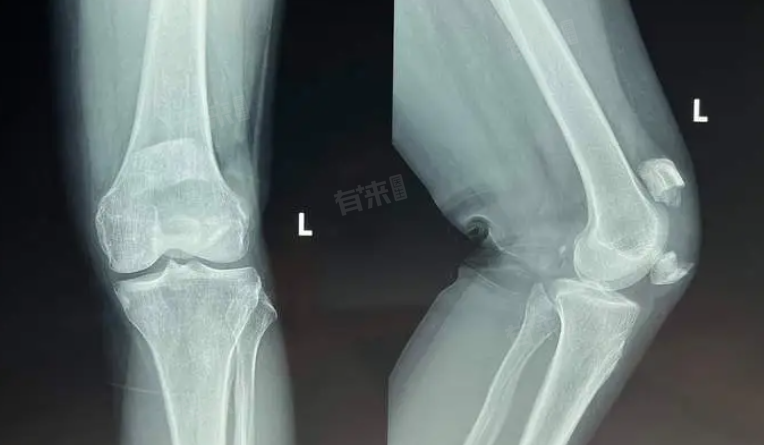

膝盖骨折后恢复走路的时间因伤势、治疗及个人体质而异,一般轻微骨折需1-2月,严重骨折则需2-3月,甚至更久,康复期间,具体取决于骨折的严重程度、治疗方式及个人体质等因素。

2、严重骨折与手术治疗:若骨折严重,如粉碎性骨折或移位明显的骨折,通常需要手术治疗,如内固定术,术后恢复时间较长,约需2-3个月,甚至更久,术后需严格遵循医嘱进行康复锻炼,逐步增加关节活动度和肌肉力量,在此期间,应避免过早负重行走,以免影响骨折愈合。